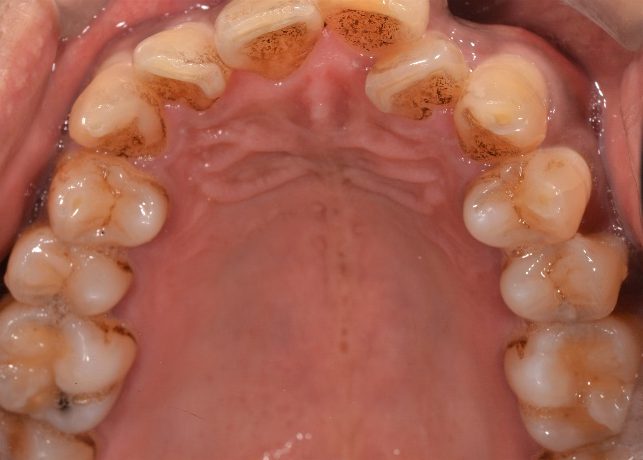

約20年の喫煙歴と毎日2杯程度のコーヒーを飲む習慣のある40代の患者様です。

今まで特に歯の痛みや気になる症状がなかったため、歯科医院は子供の頃に受診されたきりでしたが、長く歯石を取っていなかったこととタバコのヤニやコーヒーのステインによる歯の黄ばみがあることが気になり始め、数十年ぶりに受診を決意されて、当院へ来院されました。

歯科治療を長期間受けたことがないこと、歯列不正があること、長年に渡る喫煙歴やコーヒーを毎日飲む習慣があることから、レントゲン撮影に加えて口腔内写真を撮影させていただきました。

今回は、全体的にタバコのヤニやコーヒーのステインによる着色が多くみられたことから、エアフローを使用したステイン除去も行うことにしました。